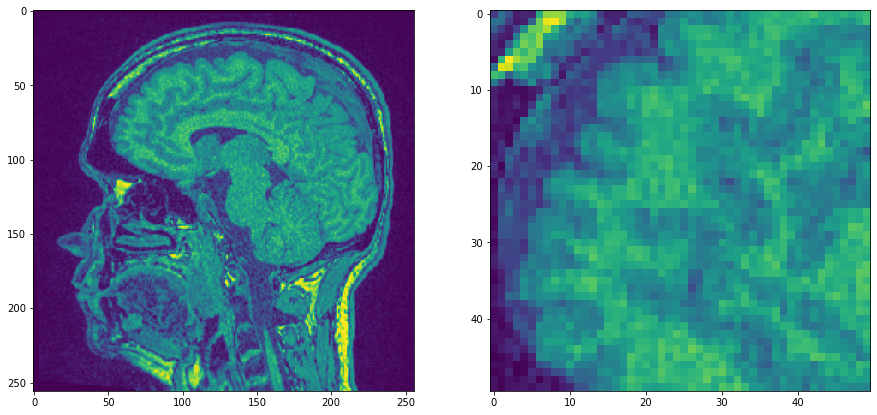

Comenzamos con un solo plano del conjunto de datos de ejemplo MRT que es bastante ruidoso y hacemos zoom.

noisy_mri = imread('../../data/Haase_MRT_tfl3d1.tif')[90]

noisy_mri_zoom = noisy_mri[50:100, 50:100]

axs[0].imshow(noisy_mri)

axs[1].imshow(noisy_mri_zoom)